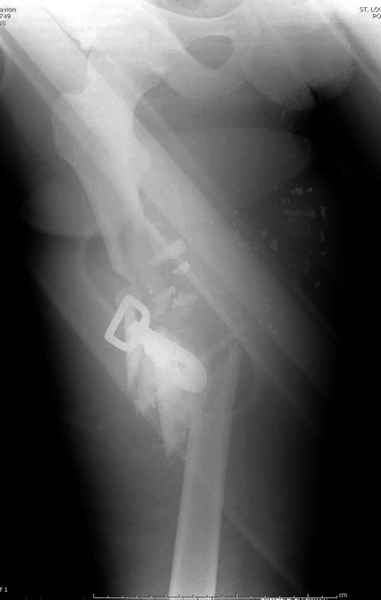

Здесь несколько примеров из нашей практики:

2 перелом бедра